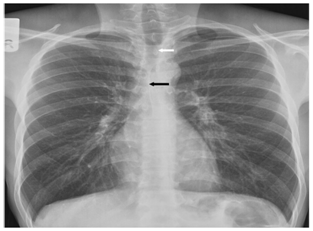

Figure 1 Chest radiograph PA view shows visualisation of anterior junction line (straight black arrow) and posterior junction line ( straight black arrow).

Figure 2 Chest radiograph PA view demonstrates presence of bulla (black asterix), alteration of normal vascular pattern assessed in right upper half (curved white arrow), presence of focal increased lucency (straight white arrow).